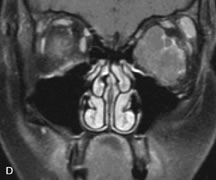

PATIENT PREPARATION Before MRI is performed, patients must be screened and prepared to avoid the potential hazards associated with the strong magnetic field. Patients who have ferrous aneurysm clips or cardiac pacemakers, who depend on life-support equipment, or who retain a possible metallic intraocular foreign body are not candidates for this imaging modality. MRI cannot be performed on obese patients who cannot fit into the bore of the magnet. Patients who are claustrophobic may not tolerate a prolonged period of study within the confines of the magnet, whereas others might do well if given a mild sedative. All worn metallic objects (e.g., necklaces, watches) should be taken off, credit cards set aside, and eye makeup removed before entering the room containing the magnet.5,20,34,35,36 NORMAL ORBITAL ANATOMY T1-weighted images provide the best anatomic details of the orbit because they display superior contrast resolution between normal structures (see Fig. 8). The vitreous has a long T1, resulting in an intermediate signal similar to brain, whereas the crystalline lens and sclera appear dark because of a longer T1 and short T2. The extraocular muscles, like all skeletal muscles, demonstrate a moderately long T1 and short T2 and highly contrast with the intense signal of the surrounding orbital fat (adipose tissue has an extremely short T1). The lacrimal glands appear as mottled areas of reduced intensity of the signal from the orbital fat in the lacrimal fossa. The optic nerves are seen with the same signal intensity as brain white matter and are hypointense relative to the orbital fat because their Tl is longer than the Tl of fat but shorter than the Tl of water. Cortical bone is not well delineated because it contains little free water, yielding minimal signal in MRI, and thus appears dark on all pulse sequences. This feature explains why MR images of the orbital apex and intracanalicular portion of the optic nerves are superior to comparable CT scans. Partial volume averaging of the bones in these regions obscures soft tissue details on CT images, whereas MRI reveals the signals only from the soft tissue structures with no cortical bone input. Bone marrow, on the other hand, is seen as a relatively intense signal because of its high fat content (see Fig. 8).37,38 T2-weighted pulse sequences are not ideal for imaging normal anatomy; however, they are particularly useful in revealing pathologic conditions (see Fig. 9). T2-weighted studies are most easily recognized by a bright vitreous signal. ORBITAL DISEASES Vascular Lesions Cavernous hemangiomas appear as well-circumscribed, smooth, usually intraconal masses that are isointense to muscle on T1-weighted images and hyperintense on T2-weighted images (Fig. 12). Patchy early enhancement is typically followed by diffuse, more homogeneous enhancement.39 The internal architecture of the mass, including septation and internal vasculature, may often be appreciated with high-quality orbital imaging.40 Lymphangiomas consist of ectatic vascular channels within a connective tissue stoma with varying degrees of lymphoid cellularity. On MRI, these tumors are typically poorly circumscribed, multicompartmental, and heterogeneous, often showing cystic dilations with fluid levels (Fig. 13). The signal characteristics within lymphangiomas vary considerably, reflecting cystic and solid components and the varying paramagnetic characteristics of blood at different stages of degradation.40–42 Acute hemorrhage appears hypointense on both T1- and T2-weighted formats. Methemoglobin present in subacute hemorrhage (3 to 14 days) leads to hyperintense signal on both T1- and T2-weighted images.41 A small percentage of lymphangiomas appear radiologically indistinct from orbital cavernous hemangiomas.43 Orbital varices are venous malformations that expand with increased systemic venous pressure, such as with Valsalva maneuvers. Because rapid acquisition of images during a Valsalva maneuver is important in imaging such a lesion, conventional or spiral CT is currently the modality of choice.44 MRI is an excellent modality for demonstrating enlargement of the cavernous sinus and dilation of the superior ophthalmic vein in patients with high-flow carotid-cavernous fistulas (Fig. 14).37MRA may be helpful in the evaluation of the venous outflow pattern. The rapidly flowing blood in these vascular structures carries the excited protons out of the section before they can be imaged, resulting in their dark appearance.5 In low-flow dural arteriovenous malformations, MRA may help define the arterial feeding vessels.45 Neural Lesions MRI is more effective than CT in delineating the intracranial optic nerves, chiasm, and optic tracts and, for this reason, is the preferred imaging modality in the evaluation of optic nerve disorders. The spatial relationships and image contrast of the orbital tissues with intraorbital optic nerve tumors is comparable between the two imaging modalities. The normal nerve is isointense to brain and appears enlarged and kinked owing to infiltration of an optic nerve glioma on T1-weighted images. Gliomas appear hyperintense on T2-weighted images and may be heterogeneous owing to cystic areas within the tumor. Contrast enhancement is variable.46 Intraorbital and intracranial optic nerve sheath meningiomas are usually isointense to cortical gray matter on Tl-weighted images and remain isointense on proton density studies (Fig. 15). Gd-DTPA is useful in delineating the intracranial extension of optic nerve meningiomas.7,47 The hyperostosis of bone and calcification associated with meningiomas are not demonstrated as well on MRI studies as on CT scans.20,37 Gd-DTPA–enhanced MRI also appears promising in the study of the permeability of the blood–brain barrier in selected optic neuropathies.22,48 MRI may reveal an enlarged optic nerve and some degree of contrast enhancement in cases of optic neuritis.49 Muscle Disorders Extraocular muscle enlargement in patients with thyroid-associated orbitopathy is demonstrated equally well with CT and MRI studies. However, the superior tissue contrast on MR images reveals better details of the relationships of the optic nerve to the thickened muscles at the orbital apex (Fig. 16).50 In addition, MRI may be able to differentiate between muscles that are enlarged as a result of edema and active inflammation and those enlarged because of fibrosis by their T2 relaxation times.21 Quantitative MRI was not found to be accurate in predicting the success of low-dose orbital irradiation.51 However, a muscular index relating the diameters of the rectus muscles to the bony orbital dimensions was useful in predicting optic nerve compression.52 MRI is also effective in imaging orbital tumors of mesenchymal origin, such as rhabdomyosarcoma, particularly in the assessment of extension into the anterior and middle cranial fossae (Fig. 17).37 The lack of any pathognomonic radiologic features necessitates rapid orbital biopsy when rhabdomyosarcoma is suspected. Osseous Lesions In general, CT is the imaging modality of choice when details of quantity and quality of bone are needed; however, abnormalities of bones can be detected indirectly by MRI. Cortical bone appears black (signal void) on MR images because of its low proton density and free-water content. The absence or discontinuity of the signal void of the orbital walls may represent bony destruction or fracture. Hyperostosis associated with prostate metastases or meningioma is visualized as areas of black smudging.50,53 Diseases in which the bone is replaced by pathologic tissues with a high free-water content, such as fibrous dysplasia, are well demonstrated on MRI. An intermediate signal intensity on T1-weighted images and hypointense signal on T2-weighted images is representative of fibrous dysplasia. Enhancement on post–Gd-DTPA MR scans is seen and is more evident in areas that are less mineralized.54 Cystic Lesions Dermoid cysts appear as rounded, well-defined lesions typically contiguous with an orbital bony suture. The high-intensity signal on T1-weighted images is attributed to the sebaceous-produced lipid contents (Fig. 18).31,50 Mucoceles may demonstrate a hypointense or hyperintense signal on MR images, depending on the concentration of proteinaceous or inflammatory fluid components. The integrity of the bony walls of the expanded sinus cavities cannot be assessed on MR as well as by CT.37,50,55,56 A high-signal intensity on Tl- and T2-weighted images is characteristic of orbital chronic hematic cysts because of the blood-breakdown products within the cysts.57 Trauma Although soft tissue relationships are usually better demonstrated on MRI, the evaluation of craniofacial bony trauma is preferable with CT. For example, prolapse of orbital fat through a fracture site and hemorrhage of adjacent tissues are demonstrated in an MR image, but the actual fractured bone is not imaged. Three-dimensional MRI of the orbit in subacute trauma has been described,58 although its precise role is not currently established. MRI has been suggested to be superior to CT in detecting intraorbital wooden foreign bodies.59,60 In a series of penetrating orbital injuries with organic foreign bodies, however, MRI was able to identify the foreign body in only four of seven cases.61 With an in vitro model for wood foreign body, McGuckin and colleagues concluded that CT was the imaging modality of choice.62 A careful history and, in selected cases, plain films to rule out a metallic foreign body are crucial before MRI is considered in patients with periocular trauma. MRI is particularly helpful in the detection and characterization of subperiosteal hematomas of the orbit (Fig. 19). They are most commonly seen in the subperiosteal space of the superior orbit as well-defined masses following a traumatic injury. The signal intensity varies depending on the acute, subacute, or chronic nature of the hematoma, based on the stage of blood degradation. Fresh hemorrhages are hypointense on T1-weighted images and hyperintense on T2 images. Hematomas that are 1 to 7 days old are hypointense on both T1- and T2-weighted images. T1-weighted images of hematomas more than a week old are hyperintense due to the oxidation of deoxyhemoglobin to methemoglobin, whereas the T2 images remain hypointense.63 Metastatic Tumors Breast carcinoma metastatic to the orbit has been demonstrated to be hypointense to the surrounding orbital fat on T1-weighted studies and hyperintense on T2-weighted images and has an affinity to the extraocular muscles (Fig. 20).50,64 The MRI characteristics of prostate carcinoma metastatic to the orbit have been described as involving the greater and lesser wing of the sphenoid, orbital roof, and optic canal. Diffuse bone hypertrophy with isointense or slightly hyperintense tissue on T1-weighted images represents the osteoblastic carcinomatous bone infiltration. Contrast enhancement is variable on T1-weighted and fat-suppressed images.65 Most other metastatic tumors also have a lower intensity signal on T1-weighted images and appear to displace or infiltrate normal orbital structures; however, their signal characteristics are variable on T2-weighted MR images.66 Many metastatic tumors demonstrate bright contrast enhancement with Gd-DTPA. Infectious Disorders MRI findings of preseptal and orbital cellulitis typically include increased signal intensities on T2-weighted images of the eyelids and orbital fat, respectively, due to the increased water content of the tissues. Since most cases of bacterial orbital cellulitis are associated with paranasal sinusitis, hyperintense signals of the affected sinuses may also be found on T2-weighted images as well as enhancement of polyps and granulation tissue on postgadolinium T1-weighted MR images. Subperiosteal abscess formation may occur due to contiguous spread of infection from the paranasal sinuses and appear on MRI as an area of intermediate signal on T1-weighted and proton-weighted MR images. The abscess may appear slightly hyperintense compared with muscle on T2-weighted scans with the necrotic contents having the greatest intensity.67 MRI and MRV are more sensitive than CT in revealing cavernous sinus thrombosis. Engorgement of the cavernous sinus, extraocular muscles, and ophthalmic veins is seen with hyperintensity of the thrombosed sinuses evident on all pulse sequences. The enlarged, thrombosed superior ophthalmic vein appears less hypointense than the normal contralateral ophthalmic vein, and hyperintensity within the lumen of the vessel may be seen on T1- and T2-weighted MR images.68 Inflammatory and Lymphoproliferative Lesions Inflammatory conditions of the orbit, both idiopathic (inflammatory pseudotumor) and those of known causes, have been found to be hypointense to fat and isointense to muscle on Tl-weighted studies and isointense or slightly hyperintense to fat on T2-weighted images (Fig. 21).50,64,69 The more fibrous or sclerosing varieties have less signal intensity on T2-weighted images. Marked enhancement is seen in pseudotumor infiltrates after gadolinium administration.70 The same signal characteristics are demonstrated in patients with Tolosa-Hunt syndrome, with mass lesions seen in the cavernous sinuses and orbital apices.71 Lymphomas have MRI characteristics similar to those of inflammatory lesions in that they are hypointense to fat and isointense to muscle on T1-weighted images (Fig. 22). They may appear hyperintense to fat on T2-weighted images, perhaps owing to less fibrosis than that seen in orbital inflammatory pseudotumor, although this is not a consistent finding.31,50,66 Lymphoid tumors typically enhance moderately after contrast injection. Unfortunately, studies have shown that tumor density and homogeneity are similar between inflammatory and malignant orbital infiltrates, and MRI cannot differentiate these lesions.72,73 Lacrimal Gland Tumors Lacrimal gland lesions present special problems in diagnosis and management. Pleomorphic adenoma (benign mixed tumor) should not be biopsied, but rather excised in toto. On the other hand, for lymphoma and inflammatory infiltrates, incisional biopsy is more appropriate than complete excision of the lacrimal gland. Thus, preoperative clinical and radiologic evaluation are especially crucial in planning appropriate surgical management. Pleomorphic adenomas demonstrate long T1 and T2 signal characteristics. They may show heterogeneity on T2-weighted images74 and moderate to marked enhancement with contrast.75 Signal characteristics of adenoid cystic carcinoma include hypointensity to fat on T1-weighted images, hyperintensity to fat with increased T2 weighting, and isointensity to fat on proton density-weighted studies (Fig. 23).31,75 Secondary bony alterations of the lacrimal fossa associated with lacrimal gland tumors, such as remodeling (benign mixed tumor) or destruction (adenoid cystic carcinoma), are seen indirectly on MR images; however, bone windows on CT scans provide better delineation of these changes. In contrast to the round or globular appearance of benign or malignant epithelial tumors of the lacrimal gland, lymphoproliferative tumors usually appear to be molding or draping onto the globe and the surrounding bony orbit. LACRIMAL DRAINAGE SYSTEM DISORDERS MRI with surface coils provides excellent spatial resolution and tissue-specific signal intensities of the lacrimal drainage system. These parameters have been found useful to more accurately demonstrate the extent of lesions in the lacrimal sac and differentiate long-standing mucoceles from solid tumors than CT.76 Physiologic studies in patients with tearing disorders now include MR dacryocystography, in which Gd-DTPA is either placed topically in the conjunctival fornix or injected by cannulation into the lacrimal sac. They provide a detailed morphologic and functional analysis of the lacrimal excretory system; however, they are no more sensitive than digital-subtraction dacryocystography or CT dacryocystography.77–79 INTRAOCULAR TUMORS On MRI, uveal melanomas have a typical appearance that helps to differentiate them from other primary and secondary intraocular tumors as well as choroidal detachments. Pigmented melanomas are hyperintense on Tl-weighted images, hypointense on T2-weighted studies, and hyperintense on proton density–weighted examinations (Fig. 24).30,31,50,80–82 These signal characteristics have been attributed to the paramagnetic properties of melanin because of stable free radicals that shorten the T1 and T2 relaxation times. Moderate enhancement is seen on postgadolinium T2-weighted images. Gadolinium-enhanced T1-weighted images are particularly sensitive in detecting choroidal melanomas.83 MRI may be less sensitive in detecting extrascleral extension of tumor than echography performed by an experienced ultrasonographer.84 Tumors metastatic to the choroid are hyperintense on T1- and T2-weighted images.24 The signal characteristics, however, may be similar to those seen with choroidal melanoma. Choroidal hemangiomas, on the other hand, have an intermediate signal on T1-weighted sequences and become hyperintense on T2-weighted images50 as well as proton density–weighted images.81 Retinoblastomas display moderate signal intensity on T1-weighted studies and a low signal on T2-weighted images.31,80,85 Calcification can be easily detected by CT and ocular ultrasonography but is not imaged by MRI.25,50 The presence of optic nerve involvement is best evaluated by MRI. ACQUIRED ANOPHTHALMIA When an eye is removed owing to tumor or trauma, an implant is typically placed in the intraconal space. MRI may be useful in defining the size, shape, and position of such orbital implants.86 Porous hydroxyapatite or polyethylene implants are preferred by many surgeons performing enucleation or evisceration. A porous implant offers the possibility of supporting a motility coupling peg to increase the movement of the overlying prosthesis. MRI with contrast is used by some surgeons to evaluate the degree of fibrovascular ingrowth in hydroxyapatite87 and porous polyethylene88 implants prior to motility peg placement. |